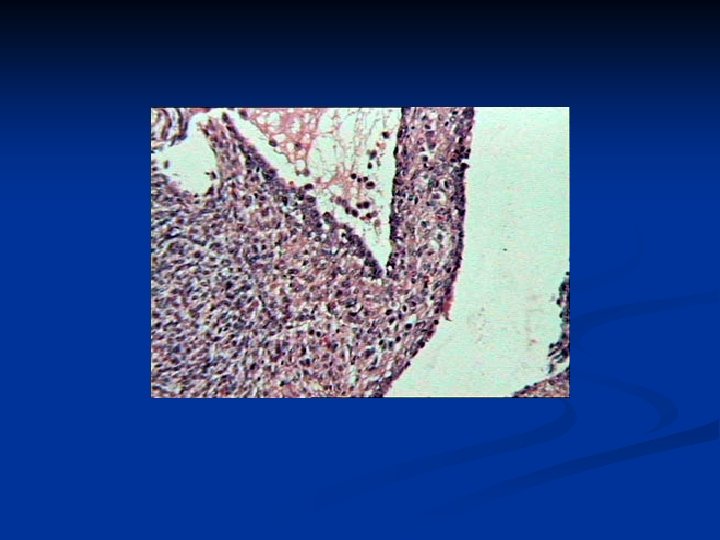

Joint Tumors Synovial tumors n Benign tumors n Tenosynovial giant cell tumor n n n Localized tenosynovial giant cell tumor Diffuse tenosynovial giant cell tumor (extraarticular pigmented villonodular synovitis, florid tenosynovitis) Malignant tumors n Synovial sarcoma n n n Biphasic (fibrous and epithelial) synovial sarcoma Monophasic (fibrous or epithelial) synovial sarcoma Malignant giant cell tumor of tendon sheath

8 -10% of all sarcomas n All ages n Location: n extremities n especially the lower extremities around the knees n n Misdiagnose benign tumor n small size, slow growth, and well-defined appearance